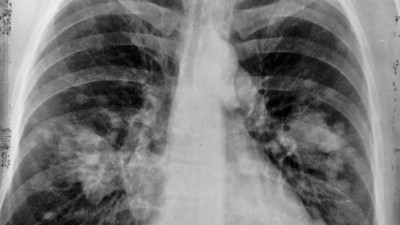

Koronanın yarattığı hasar 3 ay sonra ortaya çıkıyor. Geleneksel yöntemlerle tespit edilemiyor Korona geçiren hastalarda 3 ay sonra yeni bir tarama yöntemiyle incelenen akciğerlerinde hasar tespit edildi. Yeni hasarın geleneksel yöntemlerle tespit edilemediği açıklandı.

Korona virüsün paramparça ettiği organı açıkladı. Bilim Kurulu Üyesi uyarı üstüne uyarı yaptı Sağlık Bakanlığı Korona virüs Bilim Kurulu Üyesi Doç. Dr. Sema Turan, "Virüsün yarattığı akciğer hasarı inanılmaz. Bir yoğun bakım hekimi olarak söyleyebilirim ki gördüğümüz akciğer filmleri ve tomografileri olayın şiddetinin oldukça fazla olduğunu ve bu hasta gruplarının da zannedildiği gibi çok ileri yaş olmadığını söylemek zorundayım’’ dedi.

Bilim Kurulu Üyesi Özlü: Koronavirüs akciğerlerde kalıcı hasara yol açtı Sağlık Bakanlığı Koronavirüs Bilim Kurulu Üyesi Prof. Dr. Tevfik Özlü, koronavirüsün akciğerlerde kalıcı hasara yol açtığını ve bu nedenle çok sayıda hasta takip ettiklerini belirterek, "Bunların bir kısmı oksijen tüpüne bağlı olarak yaşamak zorunda. Bazılarında ise sürekli oksijen kullanmasalar bile efor kısıtlaması söz konusu" dedi.